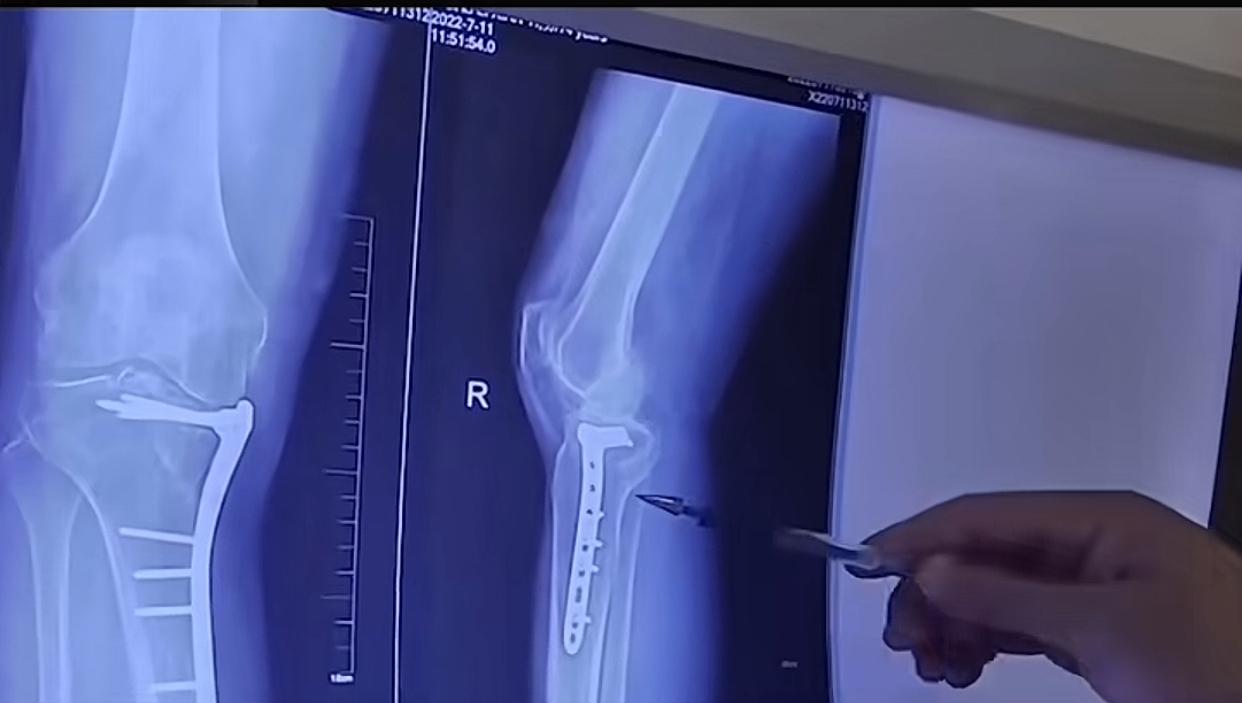

万万没想到, 好好躺着睡觉也能把骨头弄骨折! 河南一位50多岁的张阿姨,凌晨熟睡时突然发出一声闷哼,家人发现她眼神呆滞、怎么喊都没反应,掐人中唤醒后,右胳膊直接动弹不得。紧急送医检查,结果竟是肩膀粉碎性骨折,连医生都十分诧异,无摔无碰怎会如此?经神经内科联合排查,才发现是突发癫痫,肌肉瞬间剧烈收缩,硬生生把骨头“掰”断了。 无独有偶,另一位同龄阿姨更揪心,睡梦中简单翻个身,就听见骨头咔嚓作响,一查竟是脆性骨折。原来她为了保持身材常年节食,还把咖啡当水喝,骨头早就疏松成了蜂窝状,骨密度比80岁老人还要低。 这事一出,网友们纷纷热议:“太吓人了,睡觉都有健康风险”“中年后身体真的禁不起折腾,养生刻不容缓”“终于知道为啥家里老人要多补钙了”,还有网友表示“得赶紧让爸妈去查骨密度,太后怕了”。 其实这两个真实案例,给所有中老年人和注重养生的朋友提了个醒:身体的健康隐患往往藏在细节里,癫痫这类隐匿性疾病可能悄无声息找上门,而长期不良的饮食和生活习惯,会慢慢掏空骨骼健康。人到中年,别只顾着奔波,一定要给身体存够“健康本钱”,日常多吃钙含量高的食物、多晒太阳促进钙吸收,家人若出现睡眠中意识不清、肢体异常抽动等情况,千万别忽视,及时就医排查才是关键。健康从来都不是小事,别等出了问题才追悔莫及。 睡梦中骨折 中老年人健康 骨质疏松早预防 健康养生攻略